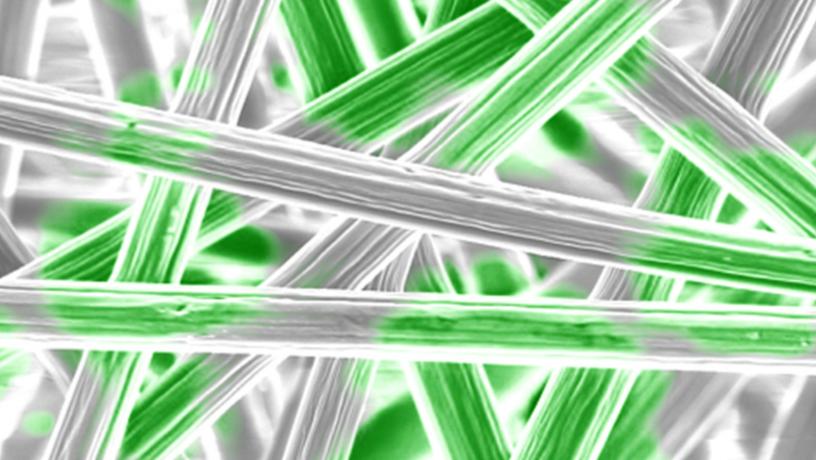

Polymer nanofibers (gray) with cartilage cell area (green) overlayed

Fluorescent imaging of calcium signaling by cartilage cells on graphite-polymer composite fibers